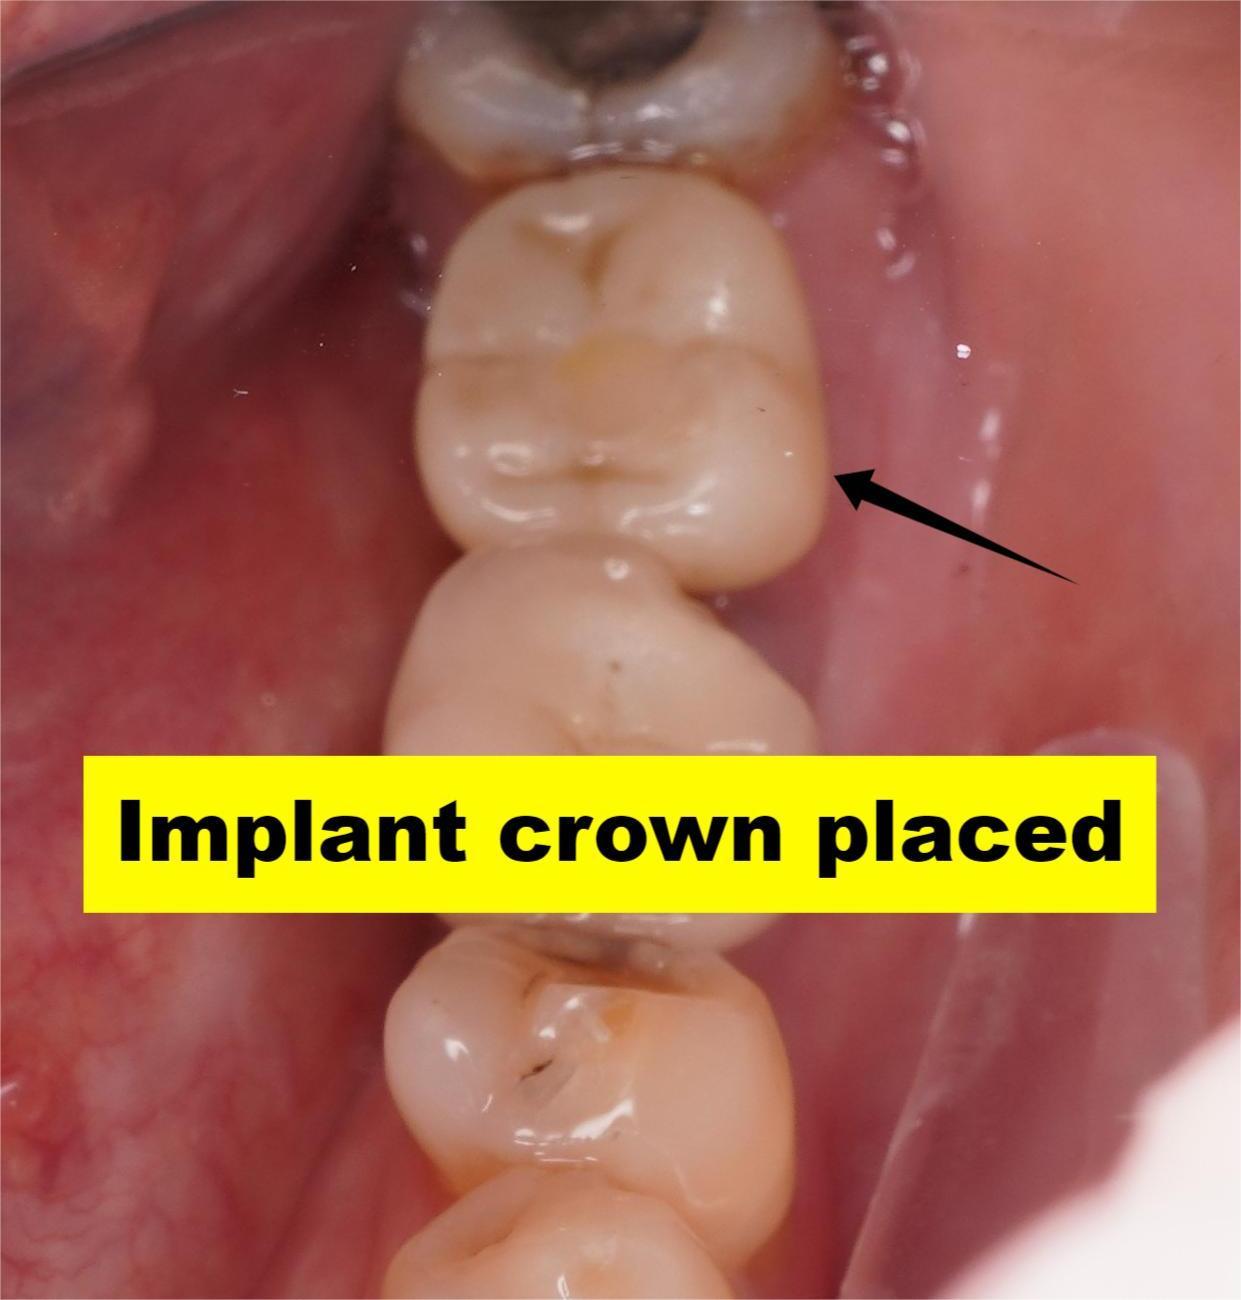

Even a perfectly placed implant can look artificial if the surrounding gums aren’t appropriately managed. Common issues with poor soft tissue management:

❌ Metal showing at the gumline

❌ Uneven gum heights

❌ Tissue recession

❌ Red or black tissue colour

❌ Unnatural contours

✅ Pink, healthy gums that match your natural teeth in color and texture

✅ Proper gum height and contours

✅ Prevents gum recession and metal show-through

✅ Natural look growing

✅ Protects implant from bacteria and bone loss

Actual patient results. Individual outcomes may vary.

Once healed, we attach the custom crown, your new tooth that looks, feels, and functions naturally.